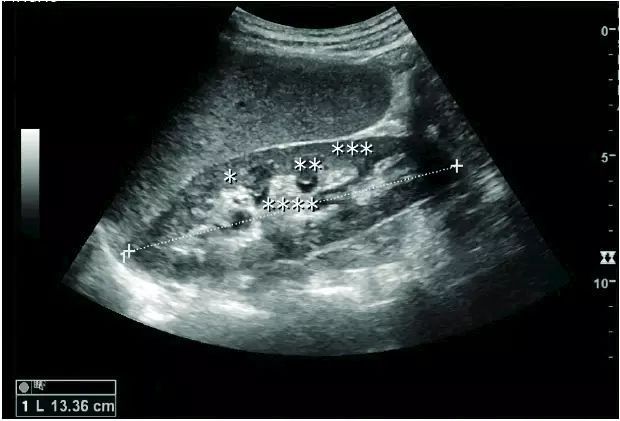

超声医学是声学、医学、光学及电子学相结合的学科,包括超声诊断学、超声治疗学和生物医学超声工程。超声成像是利用超声声束扫描人体,通过对反射信号的接收、处理,以获得体内器官的图象。常用的超声仪器有多种:A型(幅度调制型)是以波幅的高低表示反射信号的强弱,显示的是一种“回声图”。M型(光点扫描型)是以垂直方向代表从浅至深的空间位置,水平方向代表时间,显示为光点在不同时间的运动曲线图。以上两型均为一维显示,应用范围有限。B型(辉度调制型)即超声切面成象仪,简称“B超”。是以亮度不同的光点表示接收信号的强弱,在探头沿水平位置移动时,显示屏上的光点也沿水平方向同步移动,将光点轨迹连成超声声束所扫描的切面图,为二维成象。至于D型是根据超声多普勒原理制成.C型则用近似电视的扫描方式,显示出垂直于声束的横切面声象图。近年来,超声成象技术不断发展,如灰阶显示和彩色显示、实时成象、超声全息摄影、穿透式超声成像、超声计并机断层圾影、三维成象、体腔内超声成像等。

超声成像方法常用来判断脏器的位置、大小、形态,确定病灶的范围和物理性质,提供一些腺体组织的解剖图,鉴别胎儿的正常与异常,在眼科、妇产科及心血管系统、消化系统、泌尿系统的应用十分广泛。

超声图像